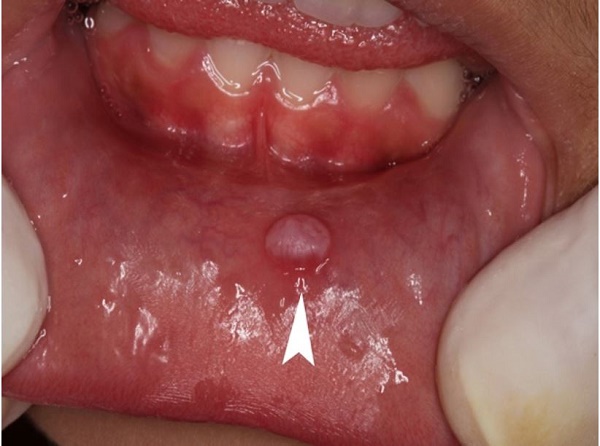

The patient, a 7-year-old Caucasian male, was referred to the oral medicine service of the School of Dentistry at Tiradentes University, complaining of a painless lesion on the lip over the last 2 months. The extraoral examination was unremarkable. The intraoral examination revealed a fibrous resilient nodular lesion on the left lower lip mucosa, with the coloration resembling normal mucosa, measuring 0.8 cm (Figure 1).